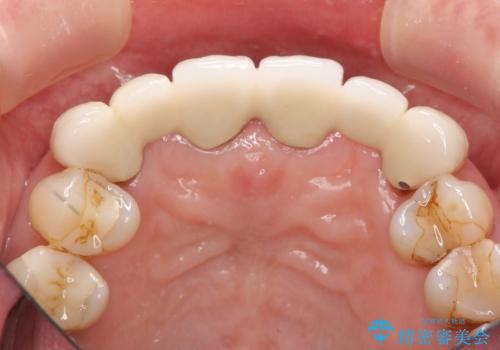

不自然な前歯ブリッジ ジルコニアブリッジによるやり替え

- 20年前に入れたブリッジの見た目の改善を求めて来院されました。

丁寧に現在装着されているブリッジを除去後、精度の高いジルコニアブリッジで審美性の改善を計画します。

- 66万円(仮歯・ジルコニアクラウン×6)費用は治療当時の料金となります

前歯に限らず拡大鏡を用いた精密な形成・シリコンを用いた精度の高い印象を徹底することで治療全体の質を高め、審美性だけでなく長期的な予後を期待することができます。